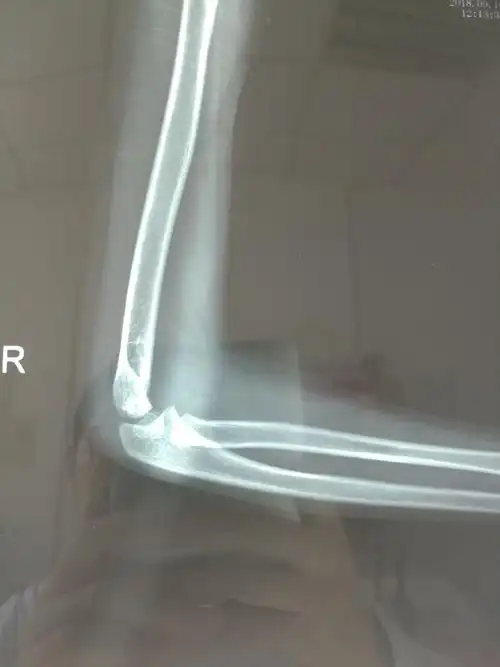

8岁,女孩,右肱骨远端骨折

如此严重的肱骨远端粉碎骨折,还能治好吗?

肱骨远端骨折

右肱骨远端粉碎骨折切开复位内固定术

儿童肱骨远端骨折

左肱骨远端粉碎性骨折一例 [病例帖]